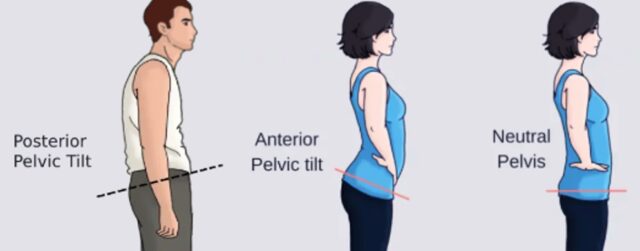

골반후방경사 골반 자세 불균형 경고 교정 운동 부터 다양한 이야기